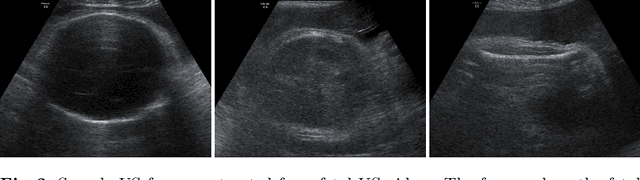

Abstract:Predicting fetal weight at birth is an important aspect of perinatal care, particularly in the context of antenatal management, which includes the planned timing and the mode of delivery. Accurate prediction of weight using prenatal ultrasound is challenging as it requires images of specific fetal body parts during advanced pregnancy which is difficult to capture due to poor quality of images caused by the lack of amniotic fluid. As a consequence, predictions which rely on standard methods often suffer from significant errors. In this paper we propose the Residual Transformer Module which extends a 3D ResNet-based network for analysis of 2D+t spatio-temporal ultrasound video scans. Our end-to-end method, called BabyNet, automatically predicts fetal birth weight based on fetal ultrasound video scans. We evaluate BabyNet using a dedicated clinical set comprising 225 2D fetal ultrasound videos of pregnancies from 75 patients performed one day prior to delivery. Experimental results show that BabyNet outperforms several state-of-the-art methods and estimates the weight at birth with accuracy comparable to human experts. Furthermore, combining estimates provided by human experts with those computed by BabyNet yields the best results, outperforming either of other methods by a significant margin. The source code of BabyNet is available at https://github.com/SanoScience/BabyNet.

Abstract:In this paper, we propose an end-to-end multi-task neural network called FetalNet with an attention mechanism and stacked module for spatio-temporal fetal ultrasound scan video analysis. Fetal biometric measurement is a standard examination during pregnancy used for the fetus growth monitoring and estimation of gestational age and fetal weight. The main goal in fetal ultrasound scan video analysis is to find proper standard planes to measure the fetal head, abdomen and femur. Due to natural high speckle noise and shadows in ultrasound data, medical expertise and sonographic experience are required to find the appropriate acquisition plane and perform accurate measurements of the fetus. In addition, existing computer-aided methods for fetal US biometric measurement address only one single image frame without considering temporal features. To address these shortcomings, we propose an end-to-end multi-task neural network for spatio-temporal ultrasound scan video analysis to simultaneously localize, classify and measure the fetal body parts. We propose a new encoder-decoder segmentation architecture that incorporates a classification branch. Additionally, we employ an attention mechanism with a stacked module to learn salient maps to suppress irrelevant US regions and efficient scan plane localization. We trained on the fetal ultrasound video comes from routine examinations of 700 different patients. Our method called FetalNet outperforms existing state-of-the-art methods in both classification and segmentation in fetal ultrasound video recordings.